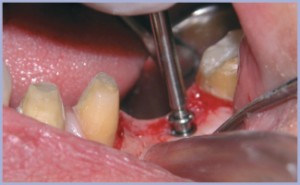

Dopo avere allestito il lembo a spessore totale (figg. 2, 3), si preparano due alveoli chirurgici, uno per l’impianto che sostituirà la radice mesiale, orientato in modo tale da risultare in asse con i carichi funzionali che si creano nella fase di entrata del ciclo masticatorio ed uno che sostituirà la radice distale, orientato in asse con i carichi funzionali che si creano nella fase di uscita. Poiché è necessario intaccare la corticale con estrema precisione, si inizia la preparazione con una fresa a palla montata su turbina (figg. 4, 5); si prosegue con il protocollo classico (figg. 6-14). Si inseriscono gli impianti, si assemblano i relativi tappi (figg. 15-19) e si sutura (fig. 20) secondo il protocollo bifase. Dopo tre mesi, quando l’osteointegrazione ha raggiunto una maturazione sufficiente ad assicurare la stabilità primaria degli impianti, si interviene con il secondo momento chirurgico per posizionare i tappi di guarigione e creare i condotti mucosi (figg. 21-24) che si epitelizzeranno in circa dieci giorni. Segue la presa delle impronte mediante transfer da impronta (figg. 25-28). Il tecnico assembla gli analoghi da gesso sui transfer, sviluppa i modelli, monta i monconi sugli analoghi ed esegue il fresaggio (fig. 29). In studio si verificano i monconi (fig. 30) e si rimandano in laboratorio per la preparazione delle cappette (fig. 31) e la relativa ceramizzazione (fig. 32).

- Fig. 4

- Fig. 5